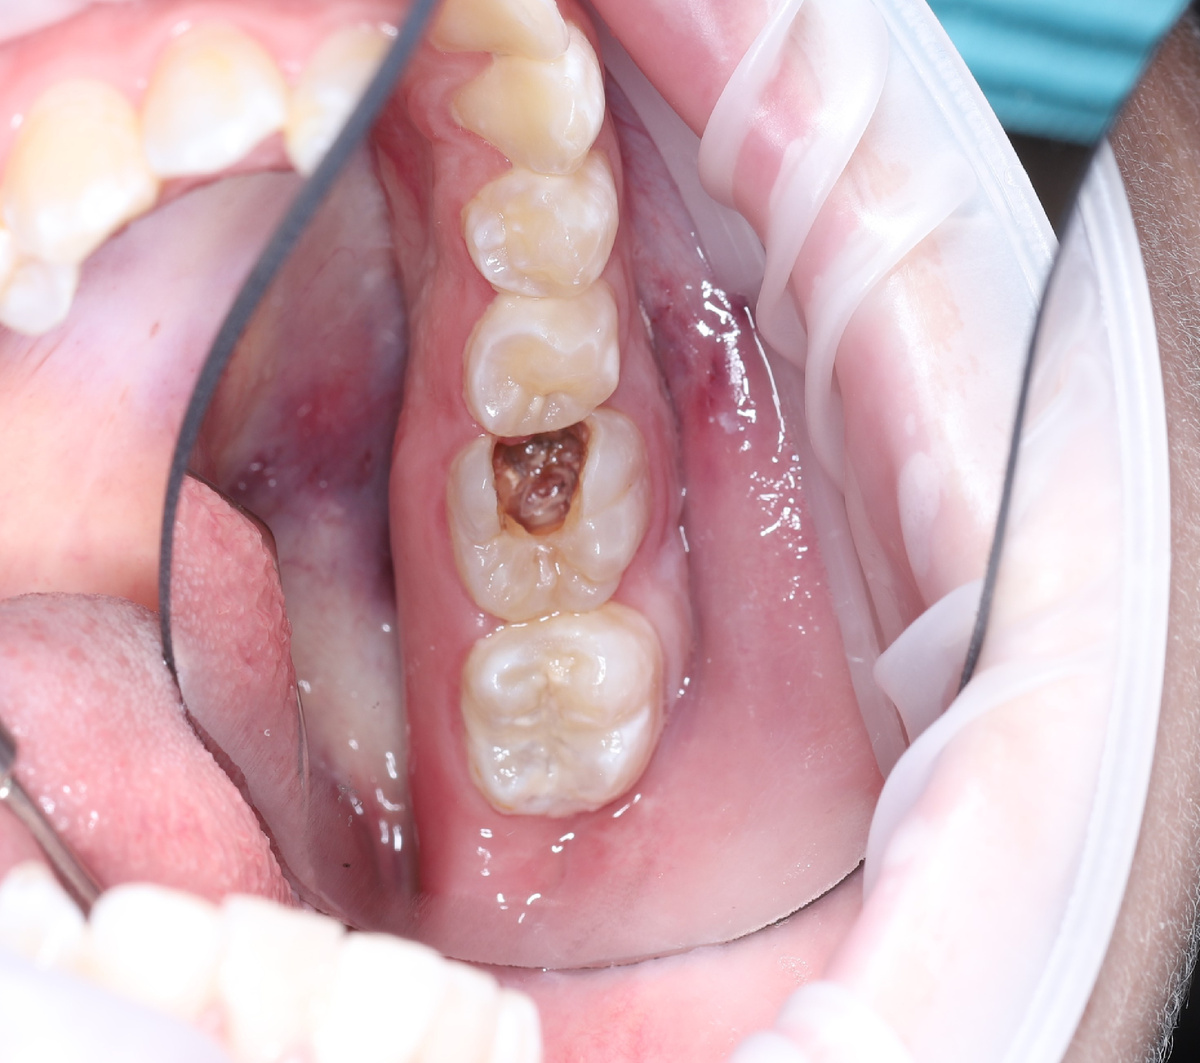

Я посмотрел у пациента в полости рта «как обстоят дела» на данный момент:

Зубик с большой дырочкой

Оказалось, что зуб болит сам по себе и при нажатии на него, имеется подвижность, примерно 2 степени. А по снимку на корнях инфекция выходит за пределы верхушки.